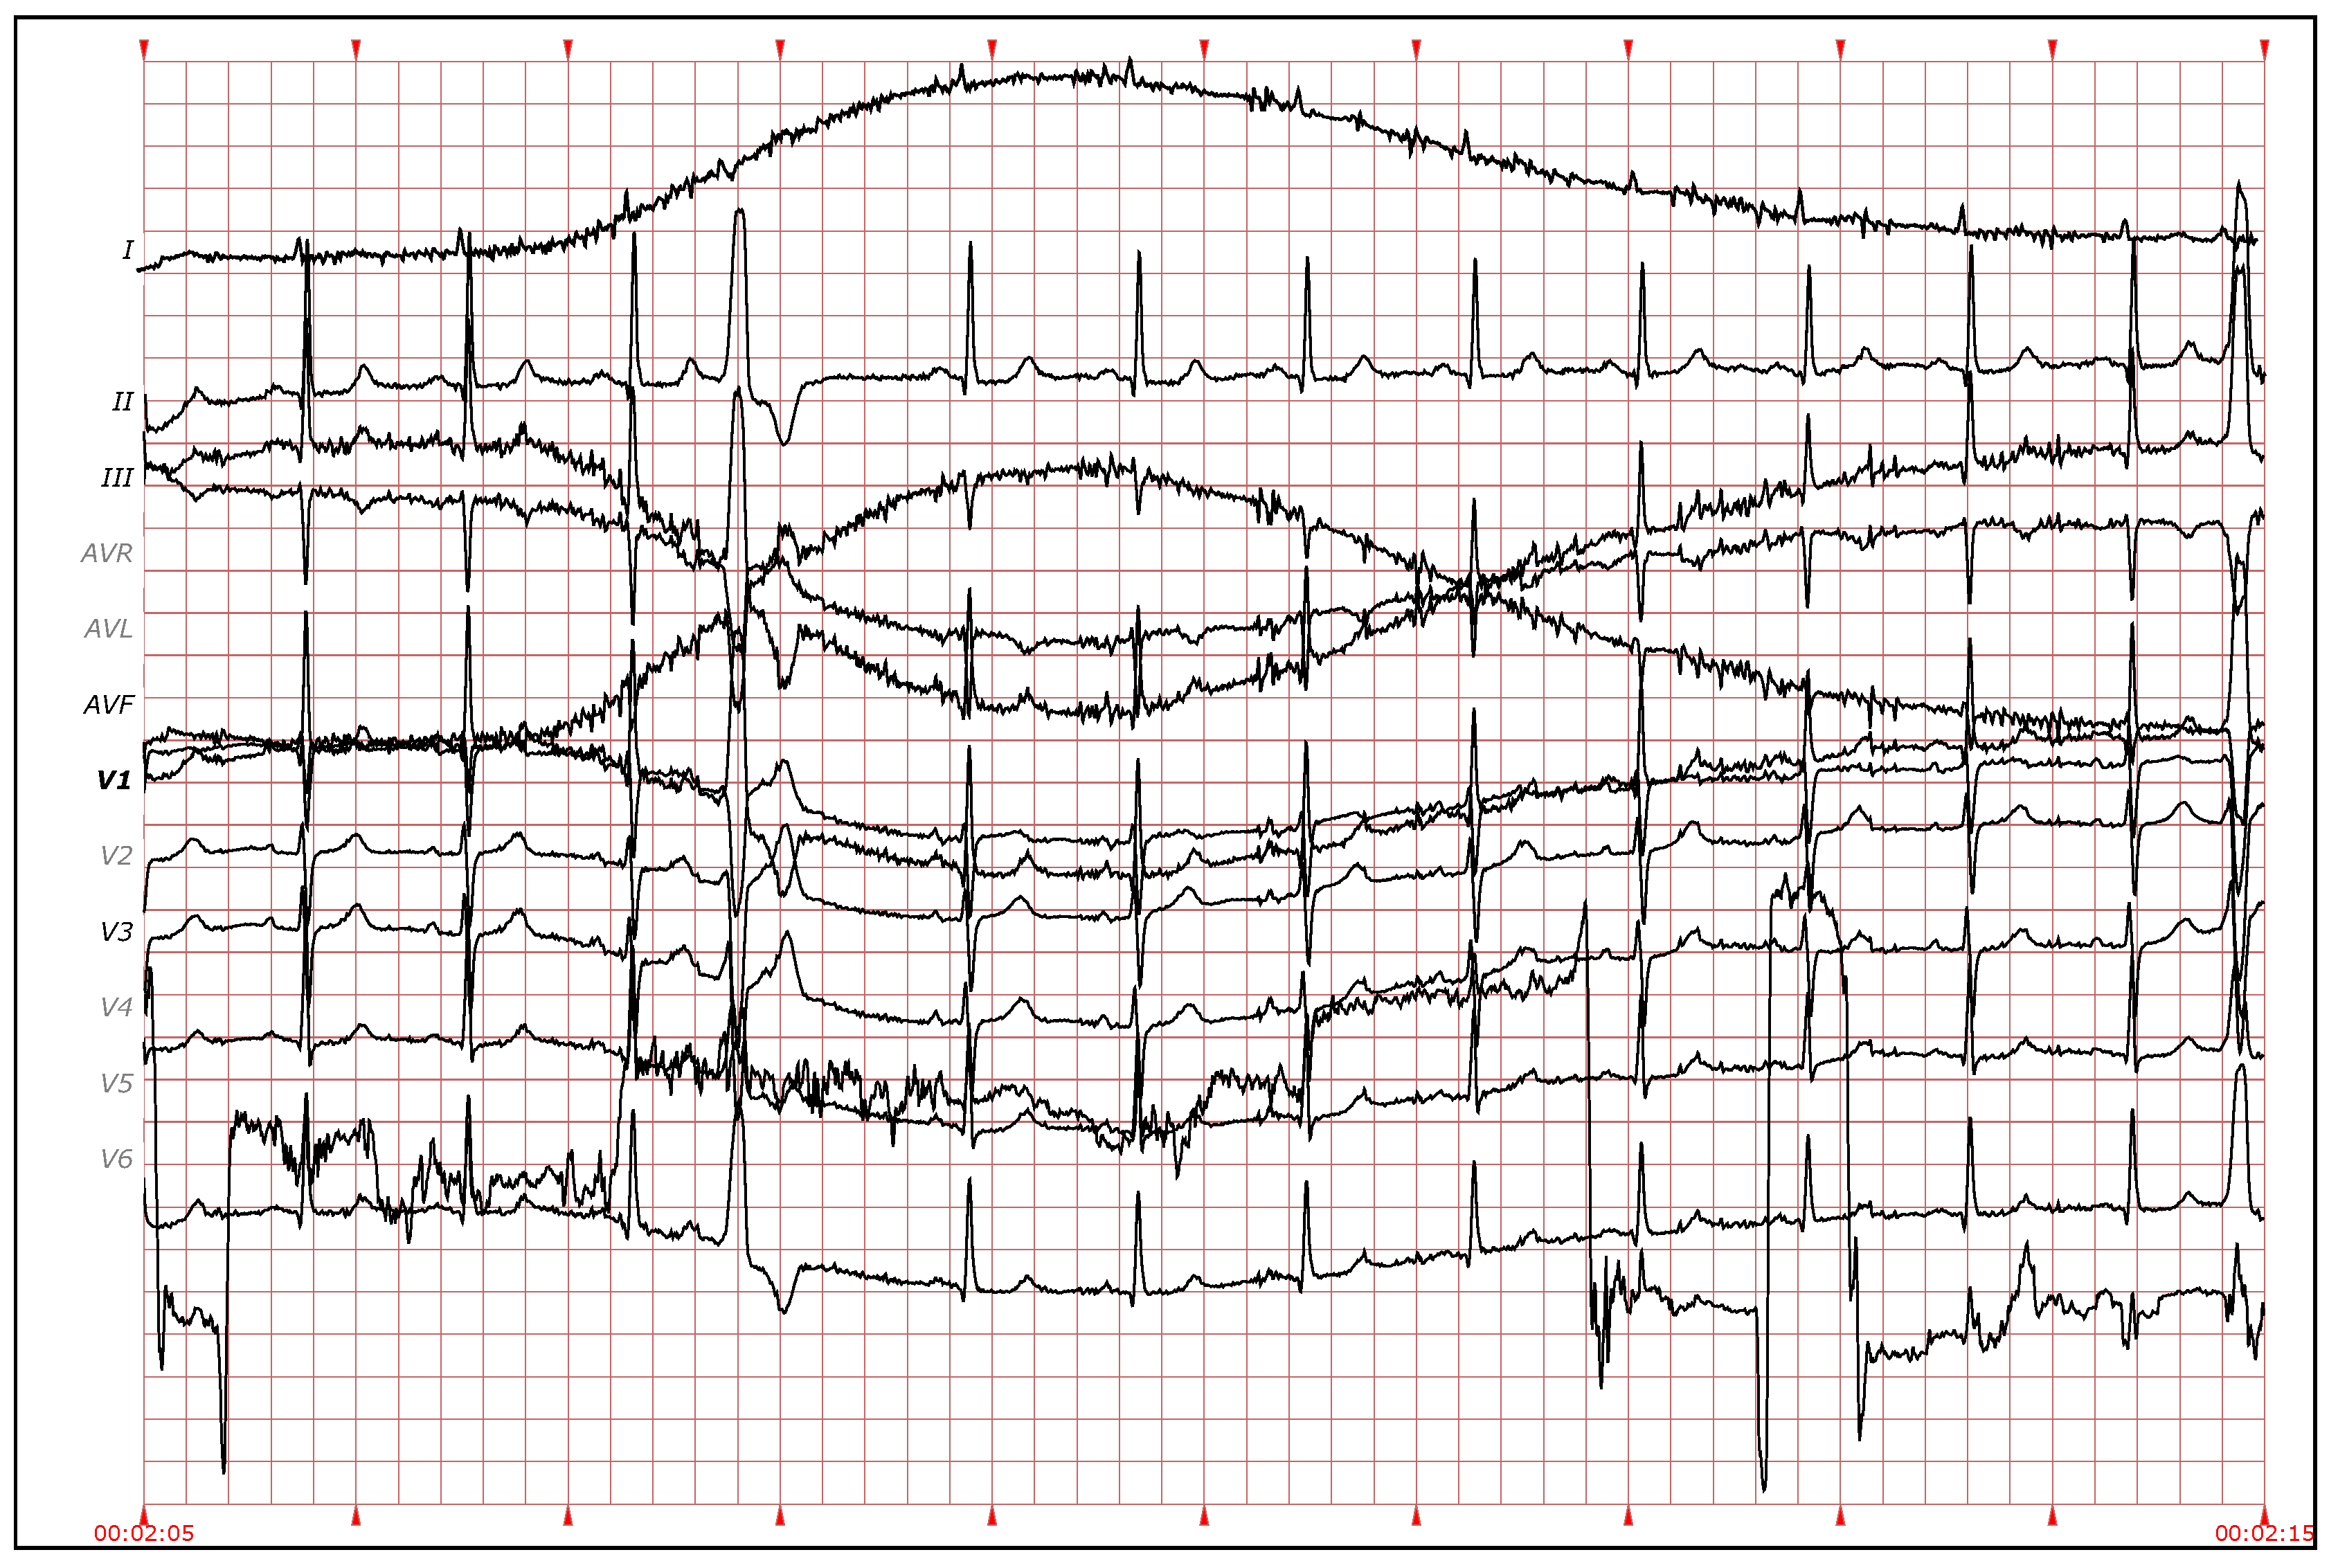

Furthermore, it is possible to see that the variation of the results (interquartile range) is also reduced by adding more leads. The 100 executions also reveal differences according to the specific leads used in that execution (I, II, etc.). This is especially remarkable when using a small number of leads. For example, in the results with two leads, some executions have an error of just 860 heartbeats in all the database, while others reach up to 1400 errors. This variability is reduced when the number of leads increases. This could be due to the bad quality of the signal in some leads (see Figure 14). The evidence obtained from those leads with noise is weak, thus worsening the results of the clustering. When a larger number of leads is used, the relative impact of selecting one of those noisy leads is less and can be compensated by the other leads. Thus, the results of using more leads not only yield higher accuracy, but also more consistence and less variability.

Figure 14.

Electrocardiogram (ECG) fragment of 12 leads. Note that some leads, I or V4, have a lot of noise, and it is difficult to distinguish the heartbeats and their shape. (Source: St. Petersburg Institute of Cardiological Technics 12-Lead Arrhythmia Database, recording I66, from 0:02:05 to 0:02:15).